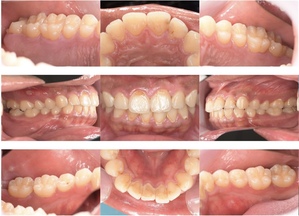

症例3

来院2回目、TBI後

症例

SRP後

初診時、TBI前

基本情報

年齢・性別 27歳・男性

主訴 主訴:左右下の歯ぐきに違和感がある

治療部位:全顎

治療内容 1.歯周基本検査、レントゲン撮影、口腔内写真、歯磨き指導、歯石除去、着色除去

2.SRP(スケーリングルートプレーニング)、再評価

その他

3.親知らずの抜歯

4.カリエス処置:右上1.2.3左上1.2.3右下6左下7CR(レジン充填)、右下7セラミックIn

5.定期検診

治療期間 6ヶ月

治療費 ※歯周基本治療の費用:PMTC以外保険診療3割負担

合計:19,680円

1.初診検査(歯周ポケット検査.レントゲン撮影):3,010円

2.歯磨き指導、歯面の歯石除去:1,410円

3.PMTC(自由診療):5,500円

4.SRP(歯周ポケット内の歯石除去)×4回:約2,000円/回

5.再評価:1,760円

(2023年12月現在)

特記事項 ・歯科医院は今回初めて

・タバコは24歳まで3年ほど吸っていたが健康のためにやめた

・親知らずは右下以外抜歯

・歯ブラシはルシェロP20M、補助用具はフロスを処方

担当者所見 全体的に歯と歯ぐきの境目に歯垢(細菌の塊)が残り、日々のホームケアで落とし切れていなかったことと、歯科医院への定期検診の習慣がなかったことから、全顎的な歯肉炎になってしまったと考えられる。

歯周基本治療とホームケアで歯ぐきの腫れや歯周ポケット、出血率などかなり改善されたが、出血がまだ0%ではない為、引き続き歯ブラシの当て方をお伝えしつつ今後は定期検診で3ヶ月おきに再発しないよう一緒に管理していく。